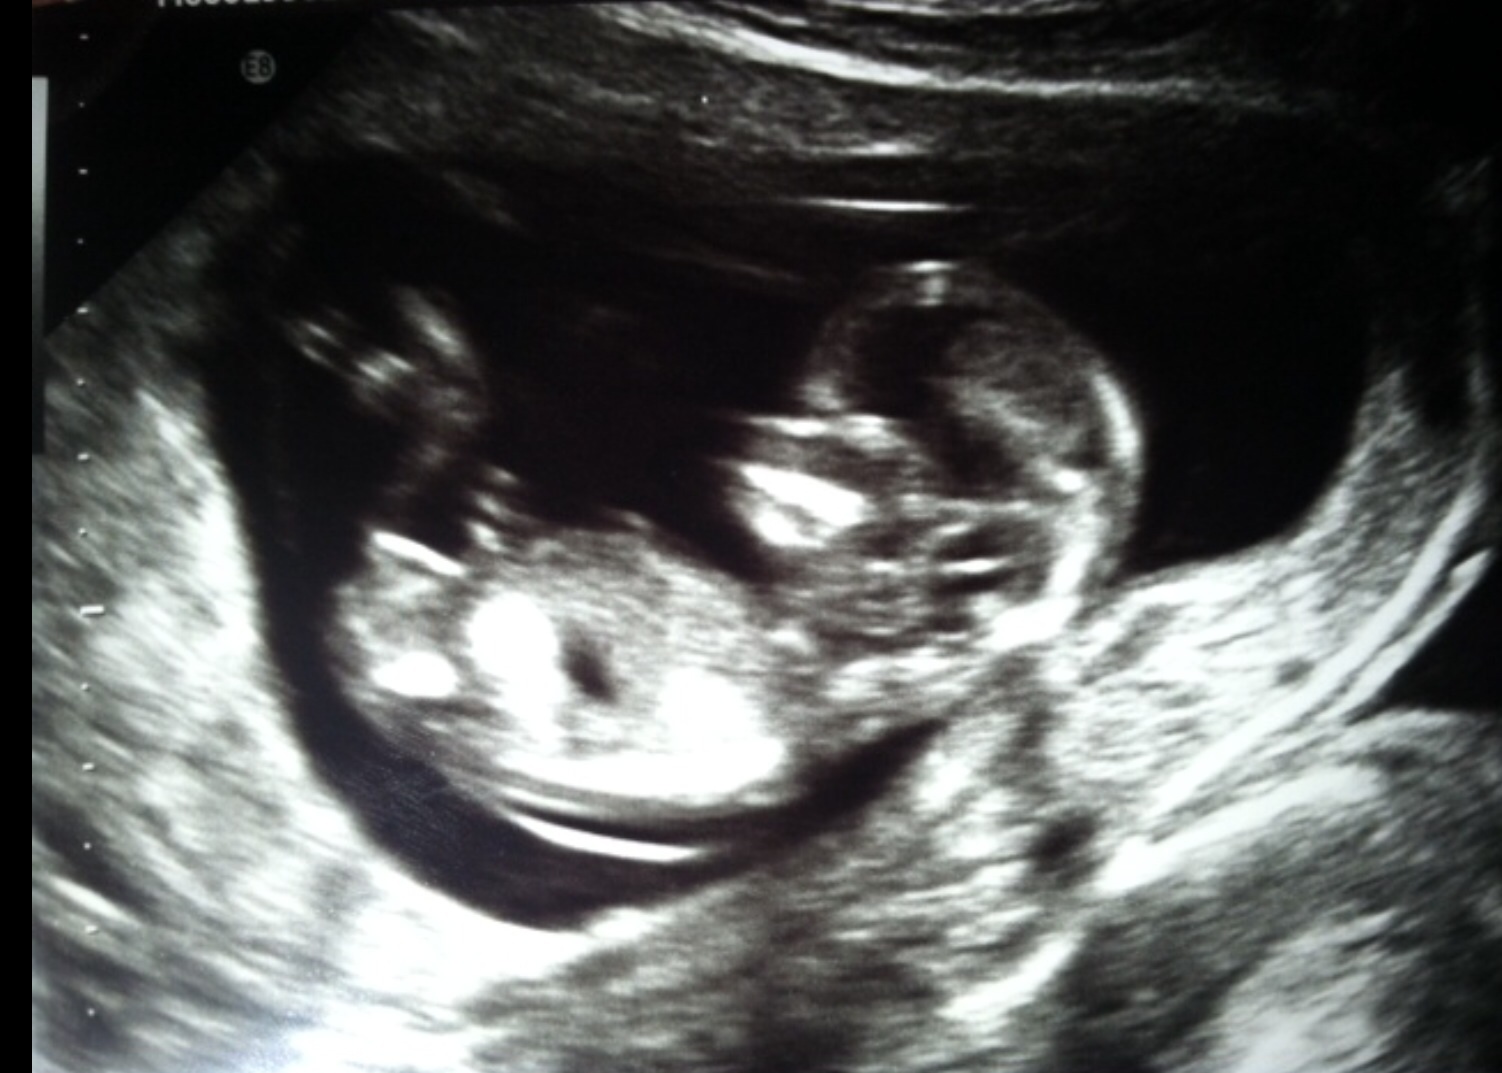

Girl

Maybe pink. Baby is pretty curled up and the leg is kinda right there, potentially blocking/obscuring any bumps. But I am thinking pink on what I can see.

I think girl also, mainly based off the skull and jaw shape. I can't really tell the angle of the dangle that well but it looks girlish haha although I'm not totally good at this just yet! Lol

18weeks confirmed. Girl!